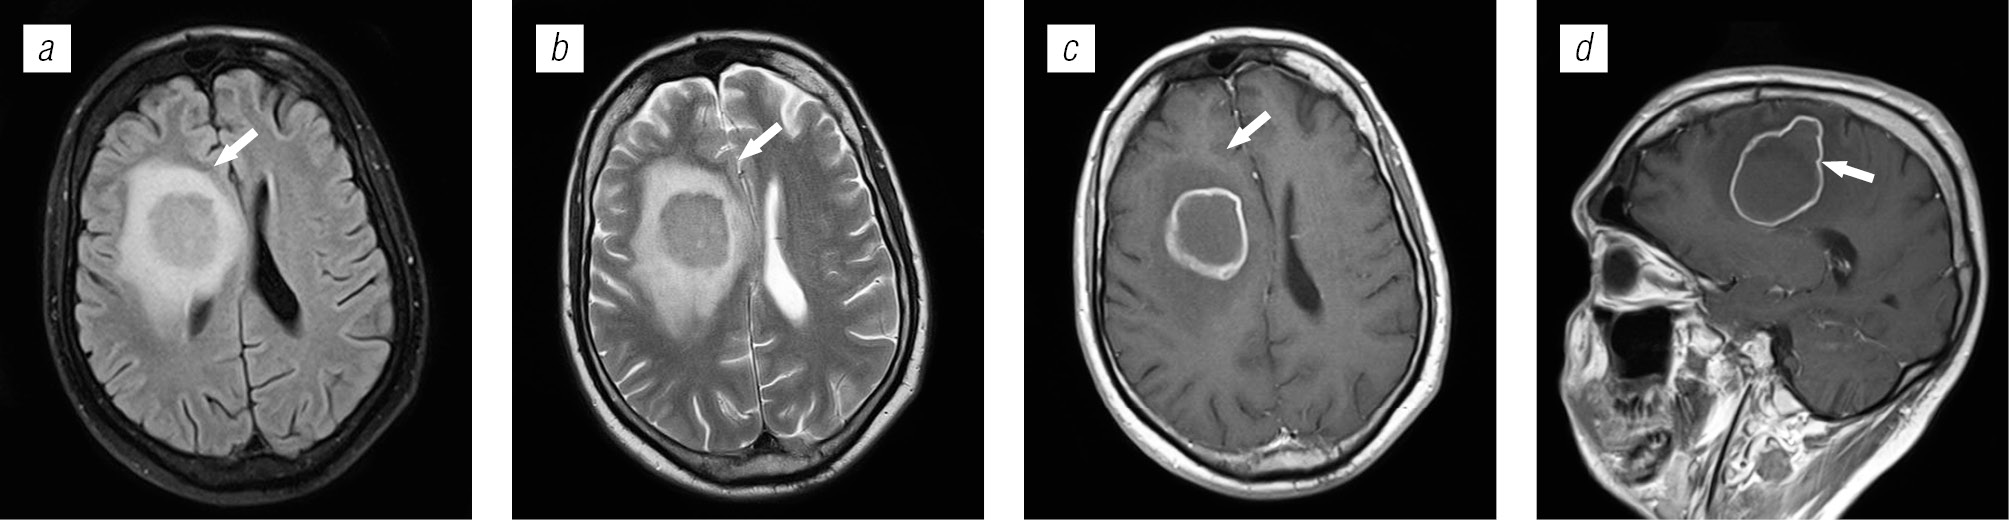

Структура оппортунистических и вторичных заболеваний была представлена токсоплазмозом головного мозга (18,3 %), герпесвирусными поражениями (12,2 %), прогрессирующей мультифокальной лейкоэнцефалопатией (10,24 %), нейроинфекцией неуточненной этиологии (12,2 %), криптококкозом (4,39 %), туберкулезом (2,44 %), лимфомой головного мозга (2,44 %), МАК-инфекцией (0,24 %).